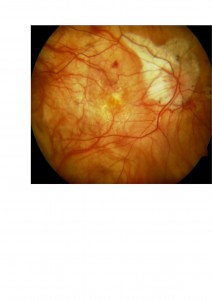

1. Maculopatía atrófica degenerativa.

En algunos casos de miopía la retina que tapiza el interior del globo ocular está tan adelgazada que podemos visualizar los vasos coroideos. La pérdida de función que conlleva es variable (desde casos leves con agudeza visual normal o casi normal a casos severos).

Poco podemos hacer para tratarla o evitar su progresión, aunque, cabe pensar que evitar la luz solar (gafas de sol), una dieta sana rica en antioxidantes y evitar el tabaquismo ayudarían a evitar el deterioro añadido por el paso de los años.